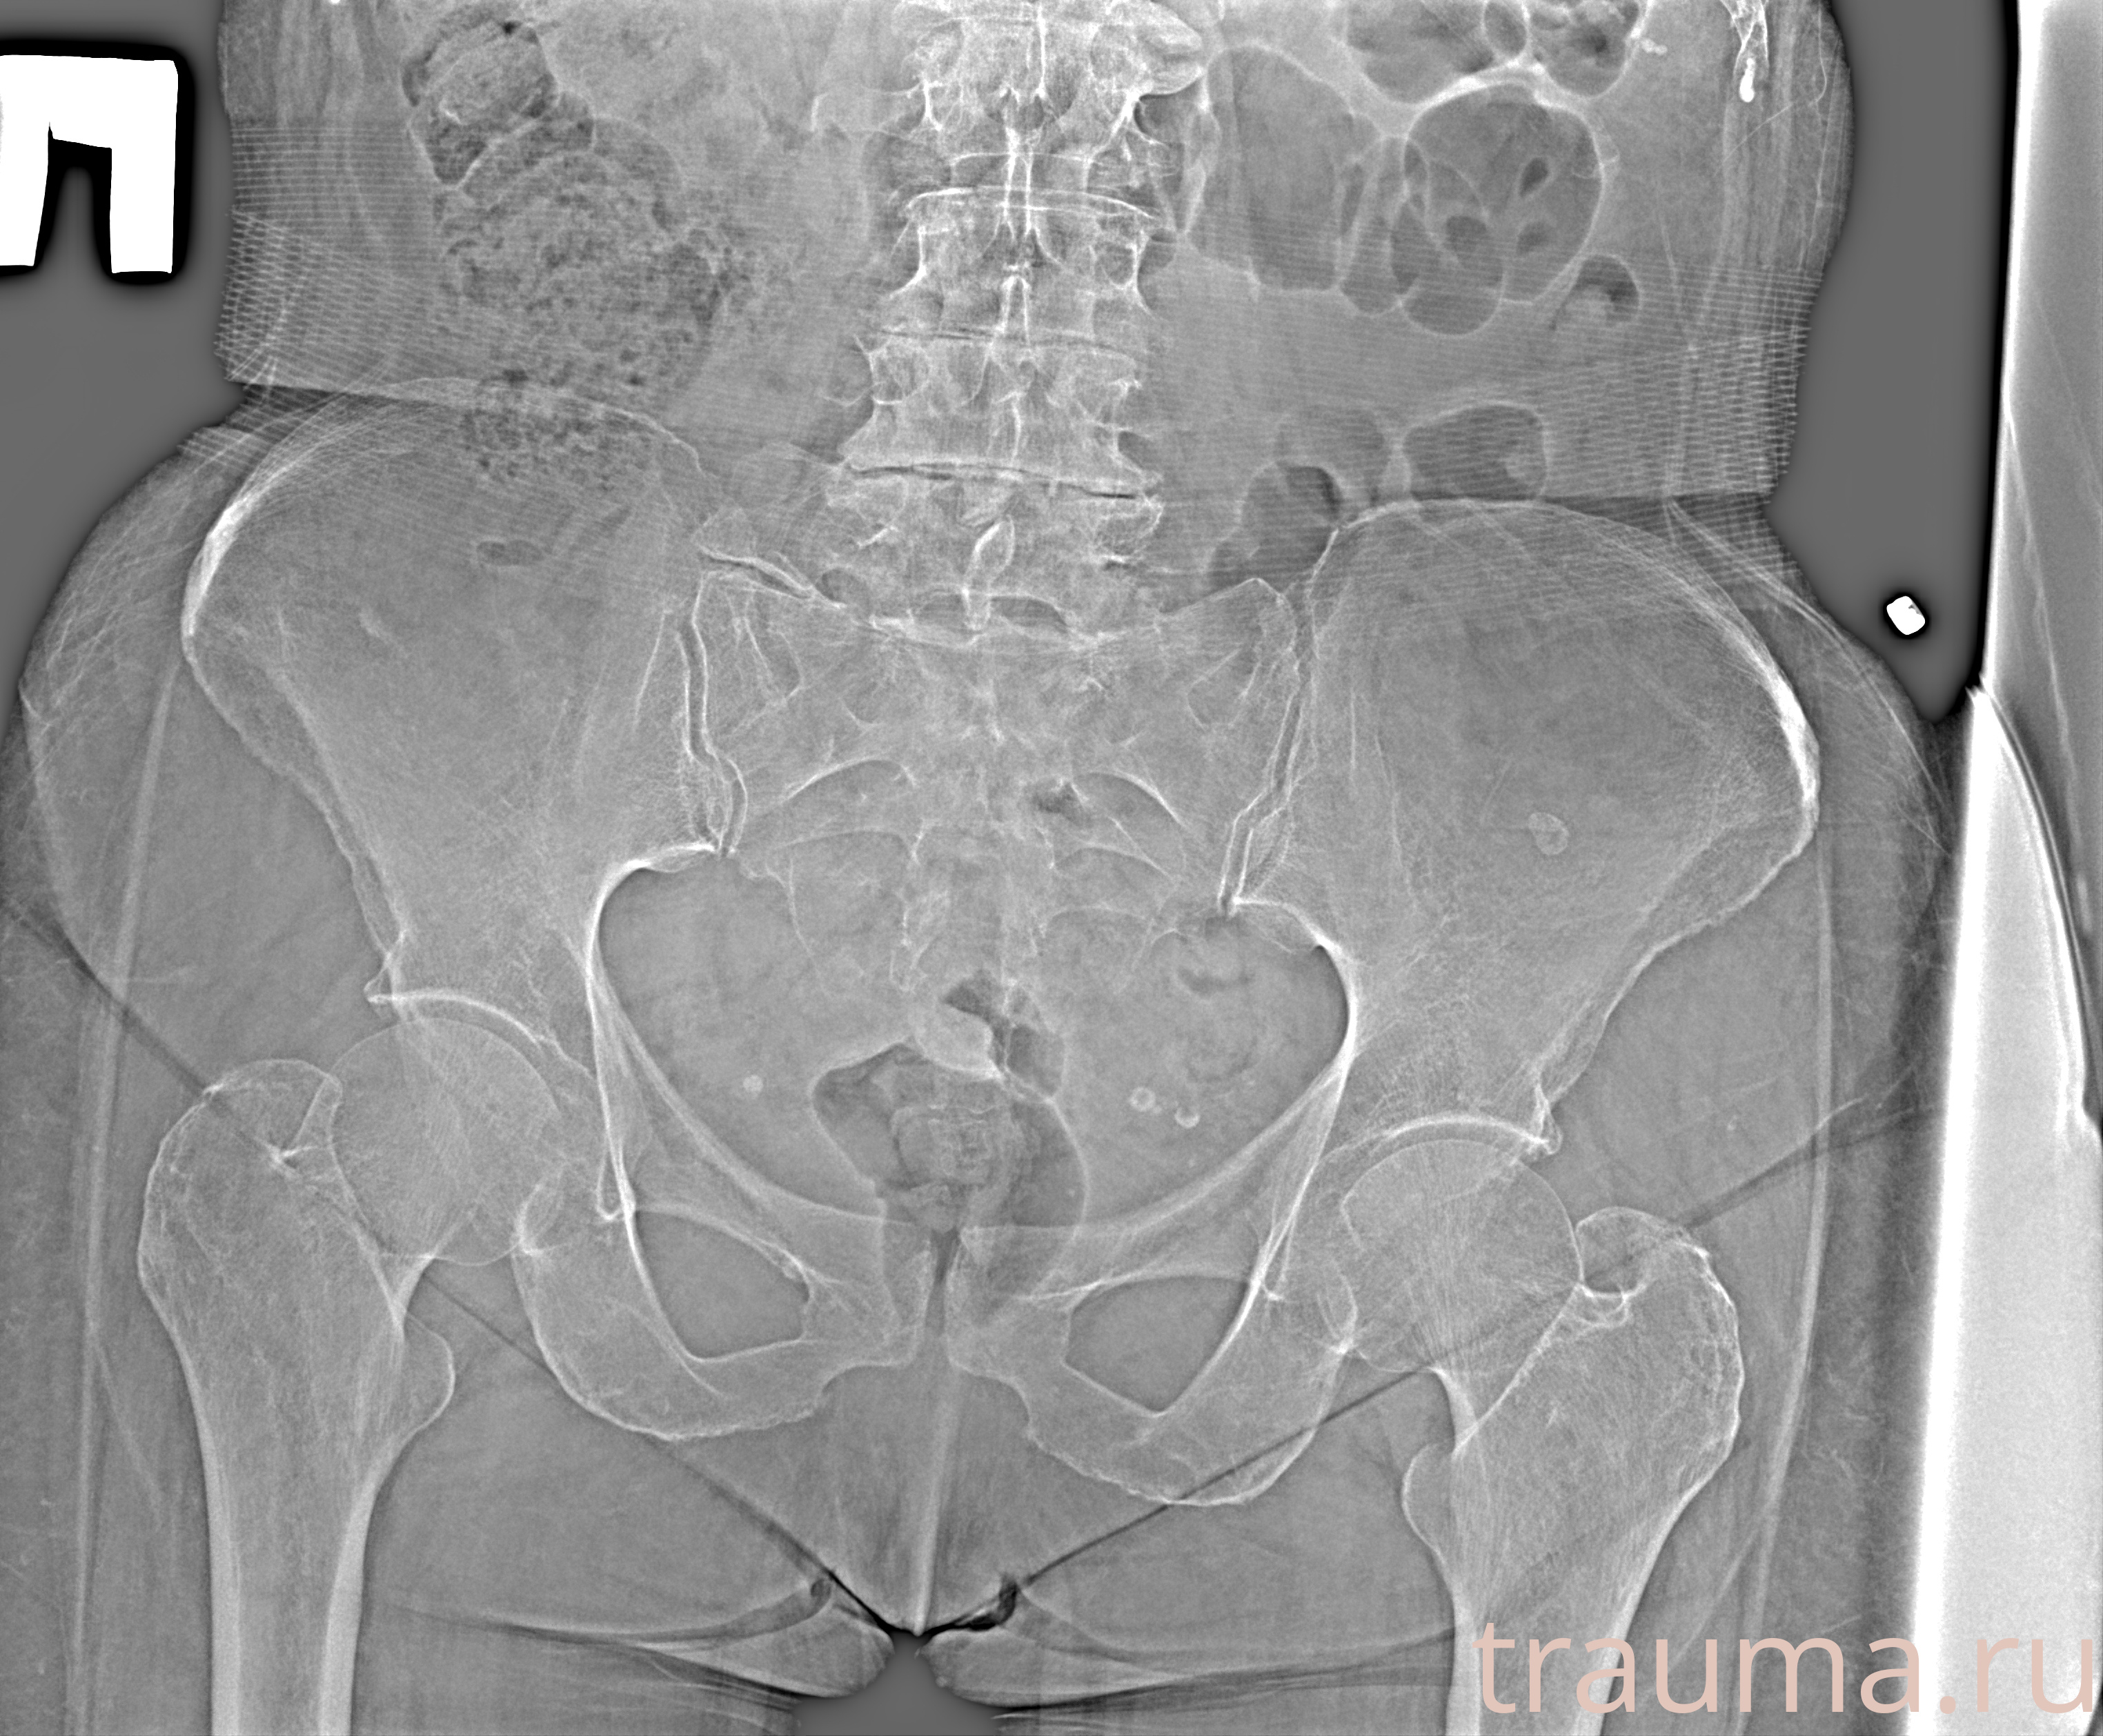

Рентген на дому: по вашему адресу приезжает врач-рентгенолог, травматолог-ортопед с мобильным рентгеновским аппаратом, проводит диагностику травмы или заболевания, делает необходимые рентгенограммы, дает рекомендации по дальнейшему лечению. Получить качественные снимки в домашних условиях возможно благодаря уникальной методике, разработанной МосРентген Центром для института  Склифосовского

при переломе шейки бедра и пневмонии от компании МосРентген Центр - партнера Института имени Склифосовского